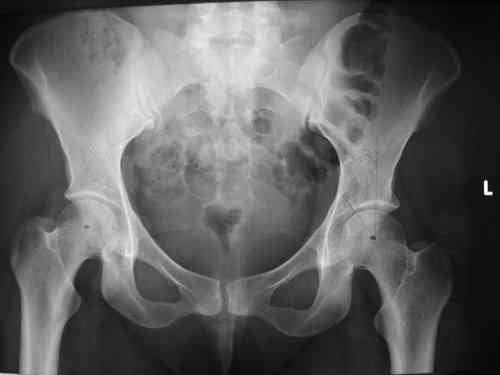

Dear group,30 years age female MVA front seat, head trauma + post column left acetabular fracture, 2.5 weeks skeletal traction. She is now conscious but still confused without any surgical treatment for brain edema.

Latest X rays and CAT is attached.Fracture within first 1.5 cm from the weight bearing dome, although AP and Obtrator oblique good, iliac oblique view reveals some displacement.I'm not sure that nonsurgical treatment will be OKHüseyin DemirorsBaskent UniversityDept of Orthopedics and TravmatologyAnkara TURKEY

My vote, given the amount of displacement on the iliac oblique and CT scan, would be for ORIF thru a posterior approach ASAP - these get pretty tough

I may get beat up for this, but I see very little displacement that concerns me on the CT. The radiograph is more concerning. I suspect it could look better, and the gap made smaller on CT. Not sure if it will affect outcome. I might give it a shot and try to see what could be done.